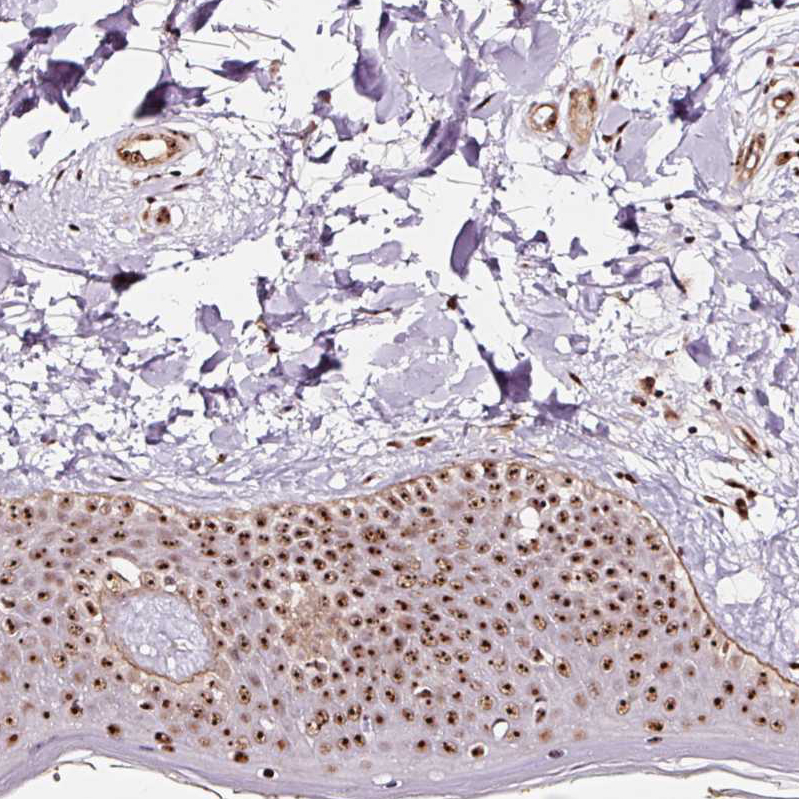

Immunohistochemical staining of human kidney, liver, skin and tonsil using Anti-GNL3 antibody HPA036743 (A) shows similar protein distribution across tissues to independent antibody HPA036742 (B).